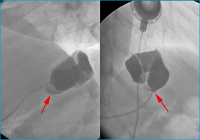

AGB

Abbildung 7: Bandleck nach AGB: Nach Anspritzen des Bandsystems zeigt sich ein kleines Leck an der Anschlußstelle zwischen Katheter und Silikonband (Pfeile).

Keywords: GastroenterologieMagenbandRadiologie